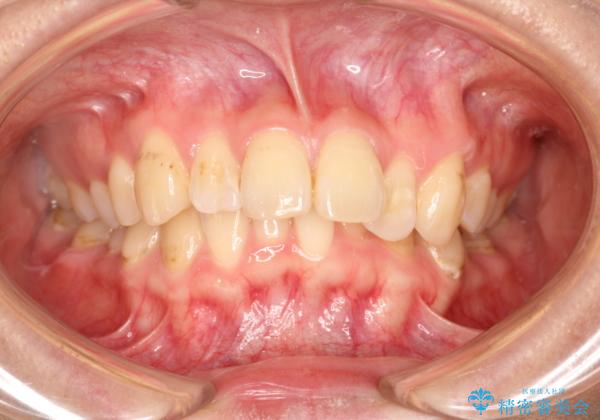

- 初診時には上顎前歯の突出、前歯部の深いかみ合わせ、叢生が見られる状態でした。

インビザラインにて不正咬合の原因除去を行うシミュレーションを念入りに制作の上、治療を行いました。

使用したインビザラインのマウスピース枚数:42枚+25枚+22枚(初回マウスピース+リファインメントが2回、1週間に1枚ペースでの交換)

このケースでは非抜歯にて奥歯を後方に移動させる事で前歯の突出を改善するスペースを作り出していますが、これはマウスピースと顎間ゴムの併用によるもので、患者様のご協力の賜物と言えます。

深い噛み合わせについてはシミュレーション上の結果と、予期される実際の歯の移動量とを考慮し、特殊なセットアップを行う事で望ましい結果を得ることができました。

治療途中でリファインメントという追加のマウスピースを製作する手順を行っていますが、その際に上下の正中を合わせたいとの要望があったため、追加シミュレーションの際に追加でセットアップを施しましたが、無事、上下の正中もご要望通りに改善しています。

使用した装置はマウスピースと顎間ゴムのみです。ワイヤーやマイクロインプラントなど補助装置の使用はありません。